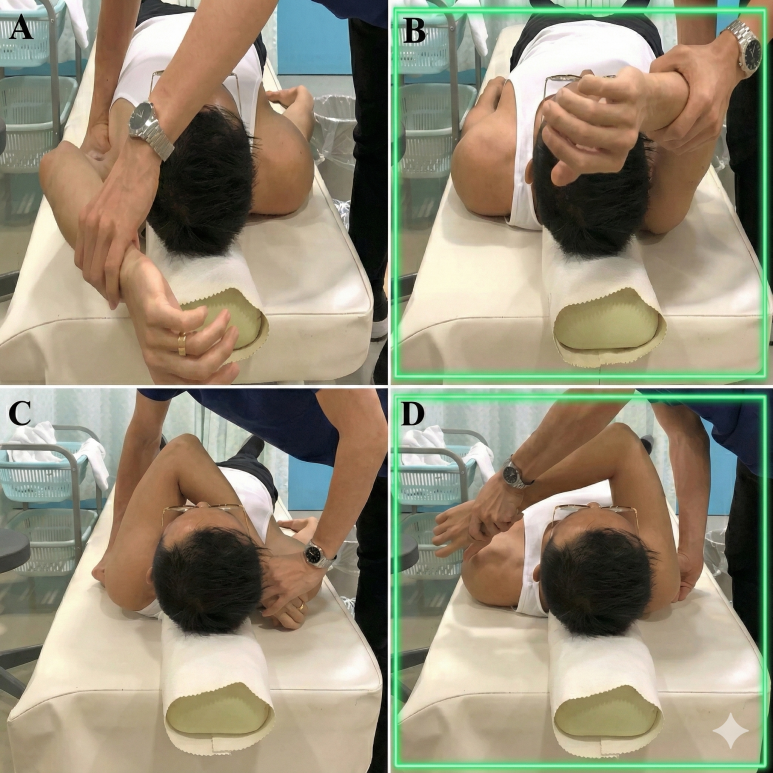

DOI: 10.7759/cureus.60157 여기서 주목한 점은 해당 선수가 SLAP 병변 외에도 어깨 관절의 '가동 범위 제한'이 심했다는 겁니다. 우리가 어깨 관절을 검사할 때 쓰는 두 가지 테스트에서 양성으로 나왔는데요. 1. 결합 외전 검사(CAT, Combined Abduction Test): 견갑골을 고정한 뒤 팔을 위로 올려(Flexion) 가동 범위가 줄어드는지 보는 검사 2. 수평 굴곡 검사(HFT, Horizontal Flexion Test): 어깨를 몸통 쪽으로 수평하게 모을 때 가동 범위가 줄어드는지 보는 검사  B,D 그림처럼 해당 검사에서 양성이라는 건, 어깨 관절의 아랫쪽과 뒷쪽이 꽉 조여져 있다는 것을 의미합니다. 정상적으로 팔을 들 때에는 어깨뼈와 팔뼈가 미끄러지듯이 움직여야 하는데, 관절이 꽉 조여 있으면이 중심축이 자꾸 틀어지게 됩니다. 이렇게 되면 팔을 올릴 때마다 SLAP 병변 위치에더 큰 압력이 가해지고,증상이 계속해서 악화되었던 것이죠. > 신경의 유착이 > > 어깨를 꽉 잡고 있다! 그렇다면 어깨 움직임을 제한하는 ‘꽉 조이는 느낌’은 어디에서 오는 걸까요? 연구진은 CAT와 HFT 검사 시 가장 심하게 늘어나는 신경을 주목했습니다. ◆ CAT (어깨 올림) 검사 시: 어깨 관절 아래쪽에 위치한 흉배신경 (Thoracodorsal Nerve, TDN)이 가장 늘어나고요. 광배근(Latissimus Dorsi) 등의 중요한 근육을 지배합니다. ◆ HFT (수평 모으기) 검사 시: 어깨 관절 뒤쪽에 위치한 액와신경 (Axillary Nerve, AxN)이 가장 늘어나고, 소원근(Teres Minor)과 같은 근육을 지배합니다. 이 사례에서는 이 두가지 신경 주변 조직이염증으로 인해 유착되면서어깨의 가동 범위를 제한하고, 결과적으로 SLAP 병변의 통증을 유발했다고 가설을 세웠습니다. 즉, 구조적인 문제가 아니라 신경 포착 증후군이 통증의 원인일 수 있다는 새로운 관점이죠. > 관절경 수술이 아닌 > > 비수술 치료 그래서 선택한 치료법이 바로 ‘하이드로다이섹션(Nerve Hydrodissection)’, 즉 신경 박리술입니다.

B,D 그림처럼 해당 검사에서 양성이라는 건, 어깨 관절의 아랫쪽과 뒷쪽이 꽉 조여져 있다는 것을 의미합니다. 정상적으로 팔을 들 때에는 어깨뼈와 팔뼈가 미끄러지듯이 움직여야 하는데, 관절이 꽉 조여 있으면이 중심축이 자꾸 틀어지게 됩니다. 이렇게 되면 팔을 올릴 때마다 SLAP 병변 위치에더 큰 압력이 가해지고,증상이 계속해서 악화되었던 것이죠. > 신경의 유착이 > > 어깨를 꽉 잡고 있다! 그렇다면 어깨 움직임을 제한하는 ‘꽉 조이는 느낌’은 어디에서 오는 걸까요? 연구진은 CAT와 HFT 검사 시 가장 심하게 늘어나는 신경을 주목했습니다. ◆ CAT (어깨 올림) 검사 시: 어깨 관절 아래쪽에 위치한 흉배신경 (Thoracodorsal Nerve, TDN)이 가장 늘어나고요. 광배근(Latissimus Dorsi) 등의 중요한 근육을 지배합니다. ◆ HFT (수평 모으기) 검사 시: 어깨 관절 뒤쪽에 위치한 액와신경 (Axillary Nerve, AxN)이 가장 늘어나고, 소원근(Teres Minor)과 같은 근육을 지배합니다. 이 사례에서는 이 두가지 신경 주변 조직이염증으로 인해 유착되면서어깨의 가동 범위를 제한하고, 결과적으로 SLAP 병변의 통증을 유발했다고 가설을 세웠습니다. 즉, 구조적인 문제가 아니라 신경 포착 증후군이 통증의 원인일 수 있다는 새로운 관점이죠. > 관절경 수술이 아닌 > > 비수술 치료 그래서 선택한 치료법이 바로 ‘하이드로다이섹션(Nerve Hydrodissection)’, 즉 신경 박리술입니다.  DOI: 10.7759/cureus.60157 1. 흉배신경 (TDN) 치료: 환자는 눕거나 엎드린 자세에서 진행됩니다. 광배근(LD), 대원근(TM), 견갑하근(SSC) 사이를 지나는 흉배동맥을 이정표(landmark) 삼아 신경 다발을 찾아냅니다. 이곳에 약침을 정밀하게 주입하여, 신경과 주변 유착된 조직 사이를 부드럽게 분리시키고요.